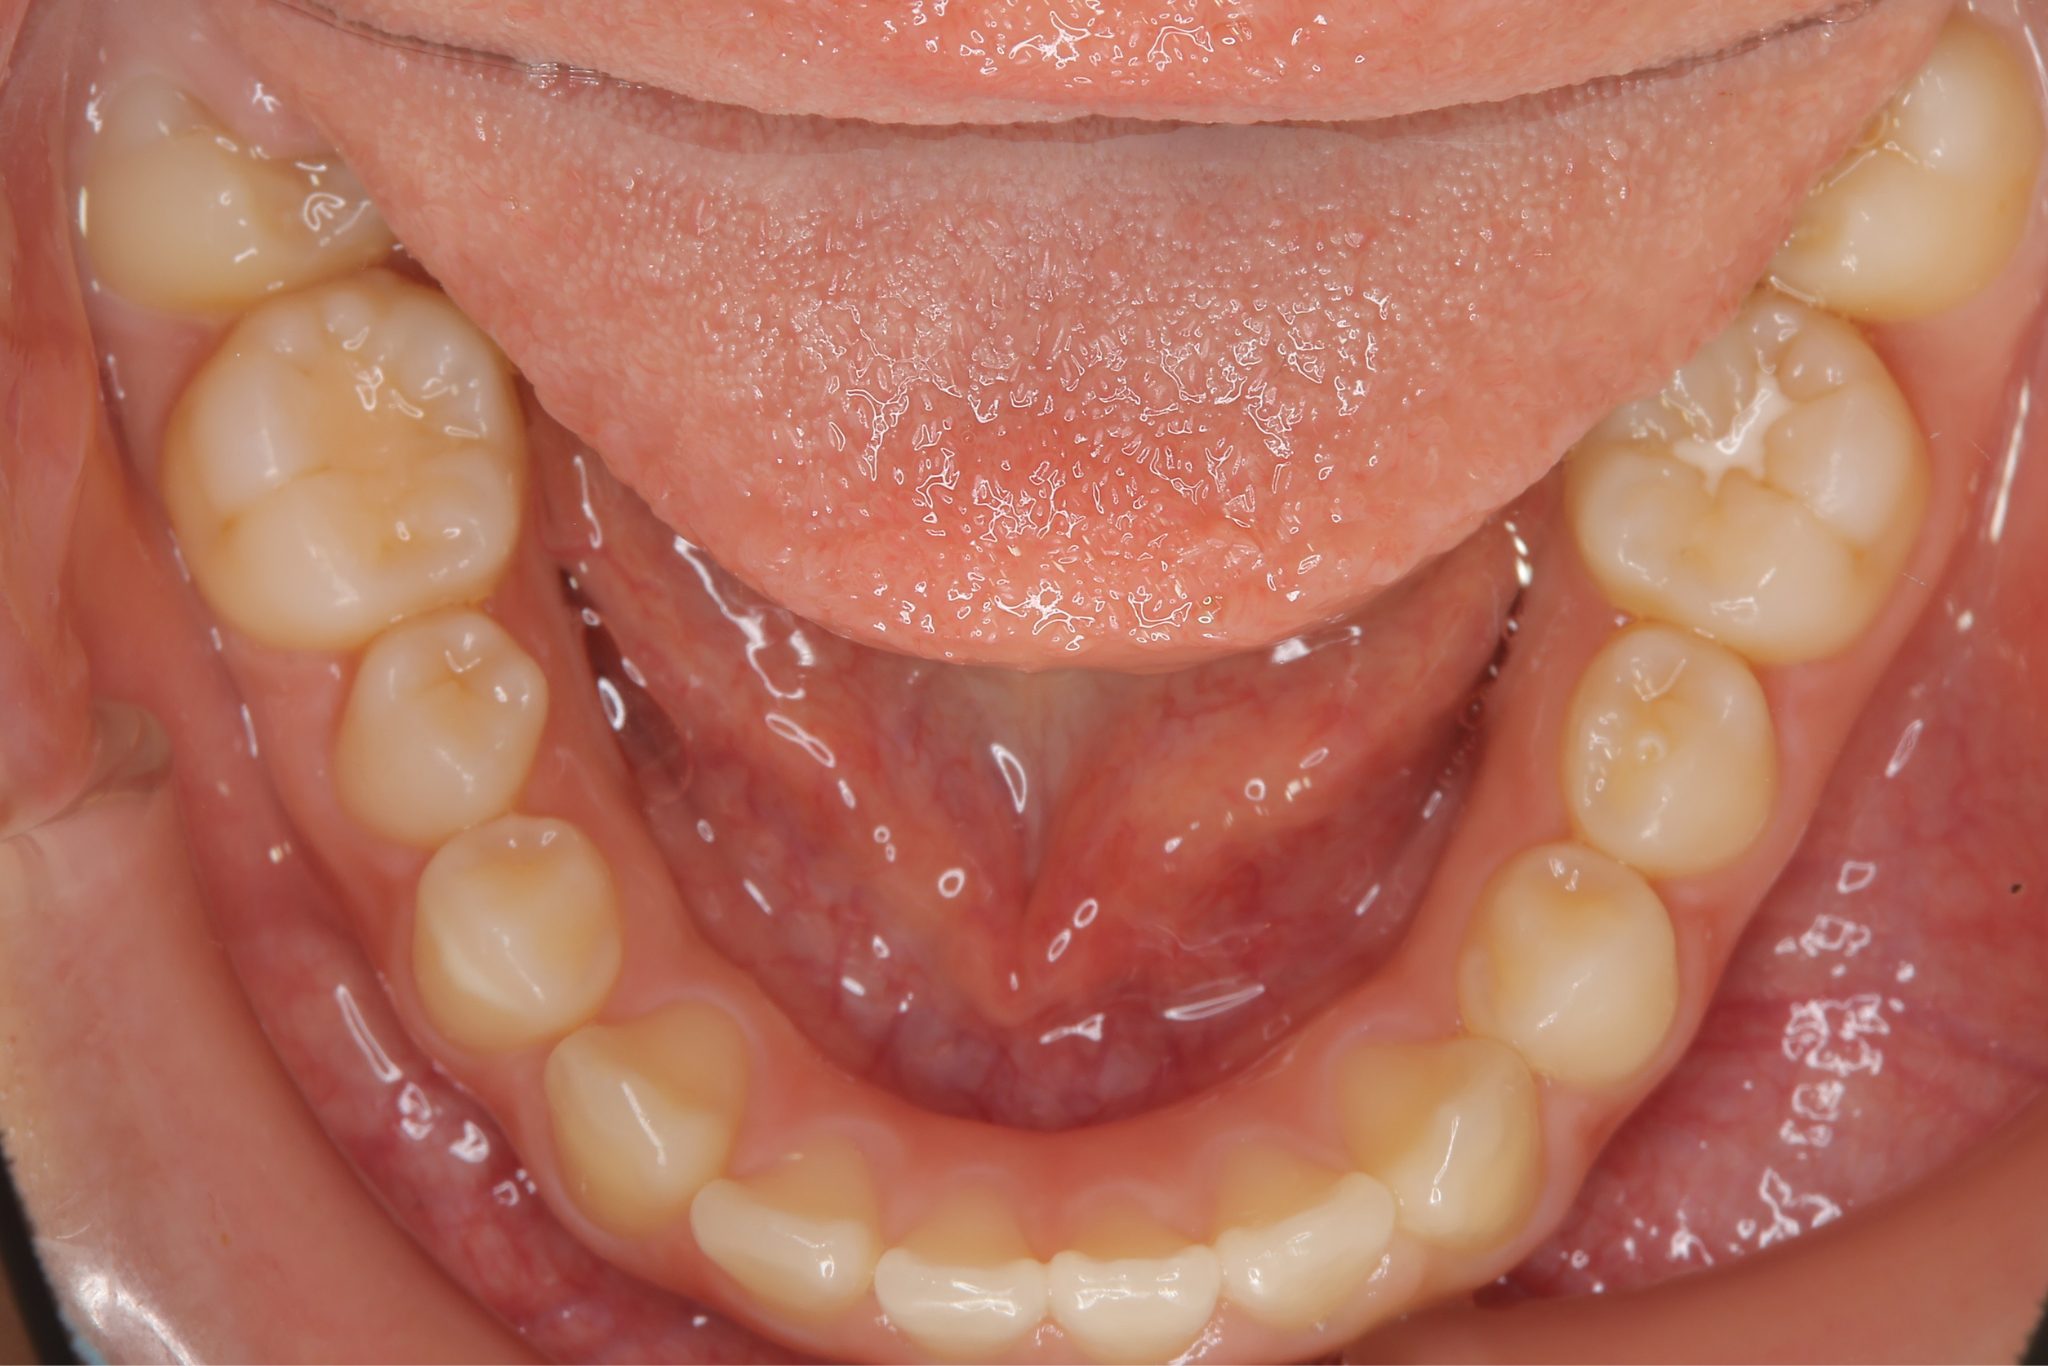

アフター

子どもの矯正治療|症例_547

施術内容 上顎急速拡大装置と下顎リンガルアーチを用いて上下顎骨を拡大した。

その後マウスピース型矯正装置で歯牙を配列し良好な咬合を獲得した。

治癒期間 2年10か月